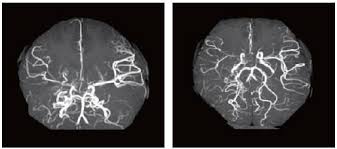

모야모야병은 뇌로 가는 주요 혈관이 점점 좁아지거나 막히는 질환입니다. 혈류가 감소하자 뇌는 이를 보상하기 위해 주변에 가느다란 새로운 혈관을 만들게 되는데, 이 혈관들이 뇌 영상에서 마치 연기처럼 보이기 때문에 일본어로 ‘모야모야’(희미한 연기)라는 이름이 붙었습니다.

◾ 정기적인 MRI, MRA 등 뇌 영상 검사 필수